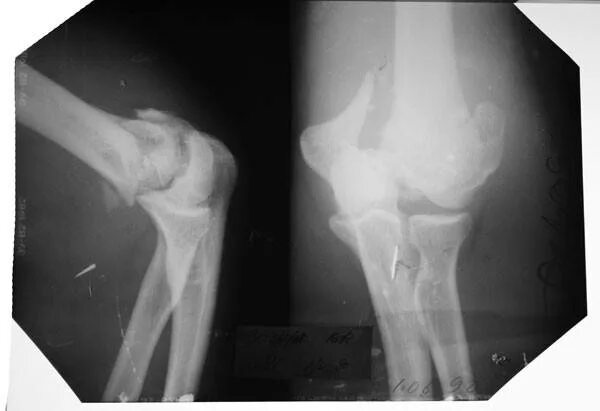

Оскольчатый перелом плеча со смещением